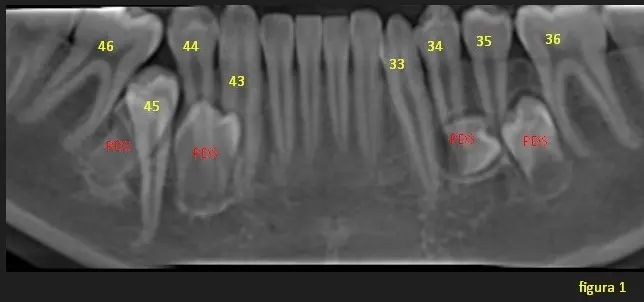

En la imágen 1, observamos a simple vista a la pieza dentaria 45 retenido sobre su eje de erupción y alrededor de esta 2 piezas supernumerarias impidiendo su normal erupcion. En el sector posteroizquierdo se observan dos piezas supernumerarias en formacion entre premolares normo ubicados.

En la segunda imagen, en una vista tangencial se observa a las dos primeras piezas dentarias supernumerarias ubicadas hacia lingual, entre zona de Pd 46 a Pd 43. Y en la imagen 3 se visualiza a las otras dos piezas supernumerarias ubicadas hacia lingual y entre pieza dentaria 33 y Pd 36.